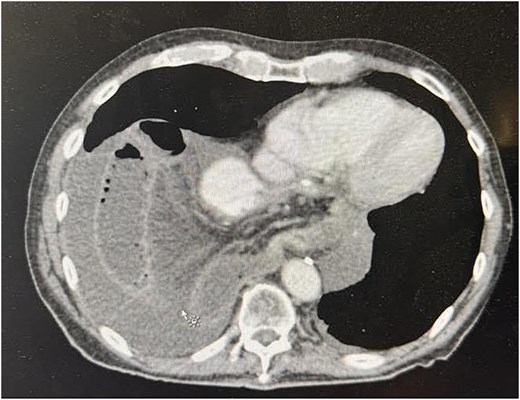

Upon arrival at the ED, the patient was afebrile and hemodynamically stable. Initial labs showed WBC 10.19, H/H 13.2/41.3, platelets 419, Na 136, K 5.3, creatinine 1.0. Portable X-ray and computed tomography (CT) imaging revealed small bowel obstruction secondary to herniation of the small bowel into the right hemithorax through a recurrent hiatal hernia (Figs 1 and 2).

Preoperative CT image showing recurrent hiatal hernia with dilated small bowel in the right hemithorax, mesenteric edema, and surrounding fluid.